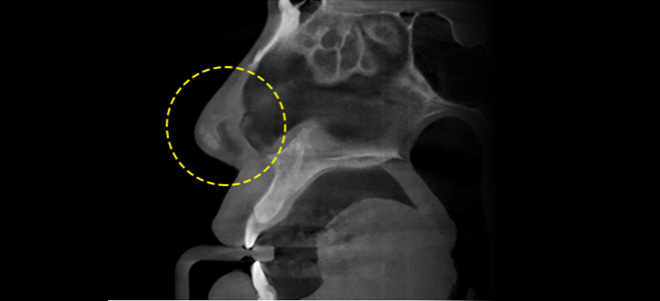

3D-CT 검사로 해부학적 구조를 파악하고 입체적으로 분석합니다.

수술 전 3D-CT 검사를 통해 코뼈, 비중격, 점막 등의 상태와 코막힘의 원인을 파악할 수 있습니다. 입체적 분석으로 정확한 수술 계획을 수립하고 합병증 발생 위험을 줄일 수 있습니다.

3D-CT로 분석하는 유형별 코 성형 솔루션

- 빠른 촬영 속도로 방사선 노출 정도를 줄인 Green16모델 도입

- 골격을 입체적으로 진단할 수 있는 3D CT

- 정확한 골격 진단을 바탕으로 섬세한 수술 계획

첨단 3D-CT장비로 일반적인 상담으로는 확인할 수 없는 문제점을 파악합니다. 코뼈와 비중격 연골, 피부조직의 상태, 비대칭을 입체적으로 분석하여 보다 안전하고 정확하게 코 성형을 집도합니다.